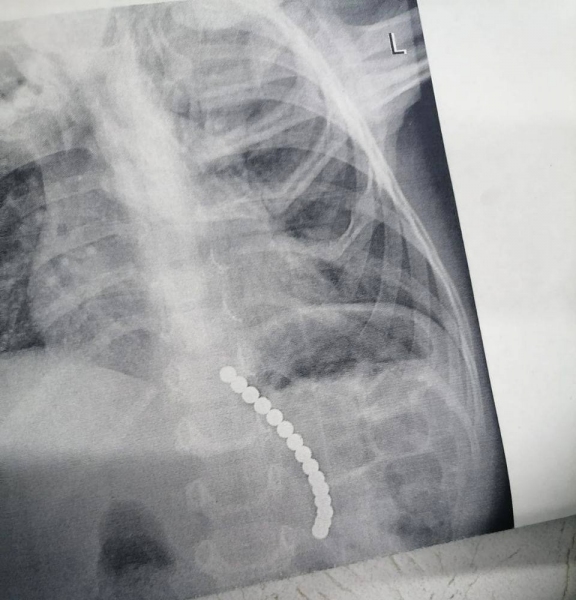

На помощь ребенку пришла дежурная смена эндоскопистов ЦДХ. Каково же было удивление медиков, когда из желудка ребенка они извлекли 15 магнитов!

Благодаря врачу ОДКБ Е.В. Милюкову и медсестре Е.Н.Ушаковой с маленьким пациентом всё хорошо.